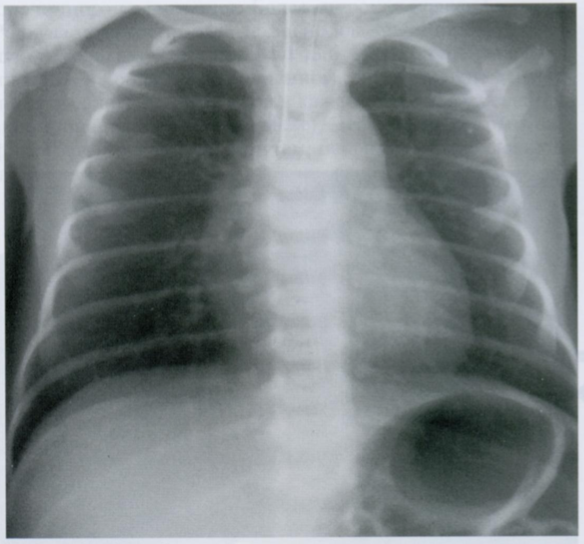

Обратите внимание на ширину ребер. Вам кажется что-то странным?

Конечно! Ребра на данном снимке утолщены.

Это может быть в результате формирования дополнительных зон гемопоэза у больных талассемией.